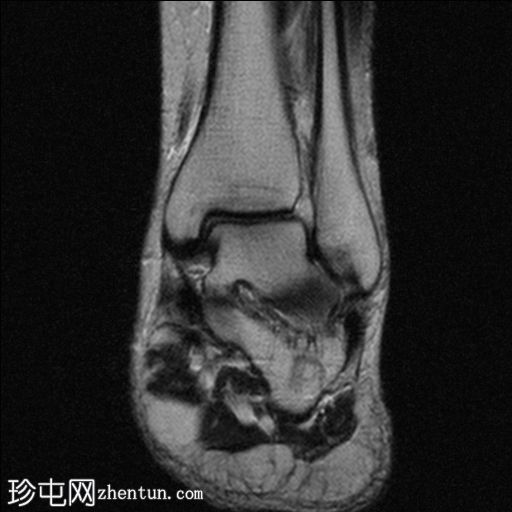

冠状面

T2

Haglund 综合征的典型表现包括:跟腱病、跟腱后(跟腱前)滑囊炎和跟骨后上部畸形(Haglund 畸形)。

这些症状是由跟骨后上骨性突起、远端跟腱以及中间的跟腱后滑囊之间的挤压引起的。

常发生于中年女性。影像学检查对于诊断 Haglund 综合征至关重要。